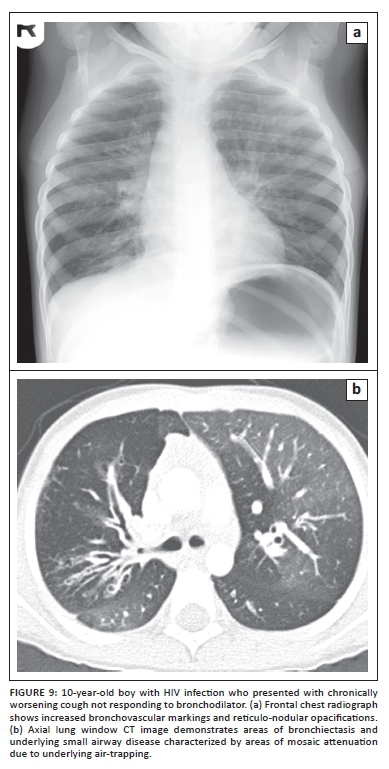

With improved survival of pediatric patients with HIV, chronic lung changes are now commonly seen in this pediatric patient population. On chest radiographs, increased bronchovascular markings, reticular and/or nodular pattern opacifications, cavities, cysts and bronchiectasis may present.20,21 CT is beneficial for characterising these chronic changes as well as guiding surgical planning such as lobectomy for focal, severe, and non-reversible bronchiectasis (Figure 9).